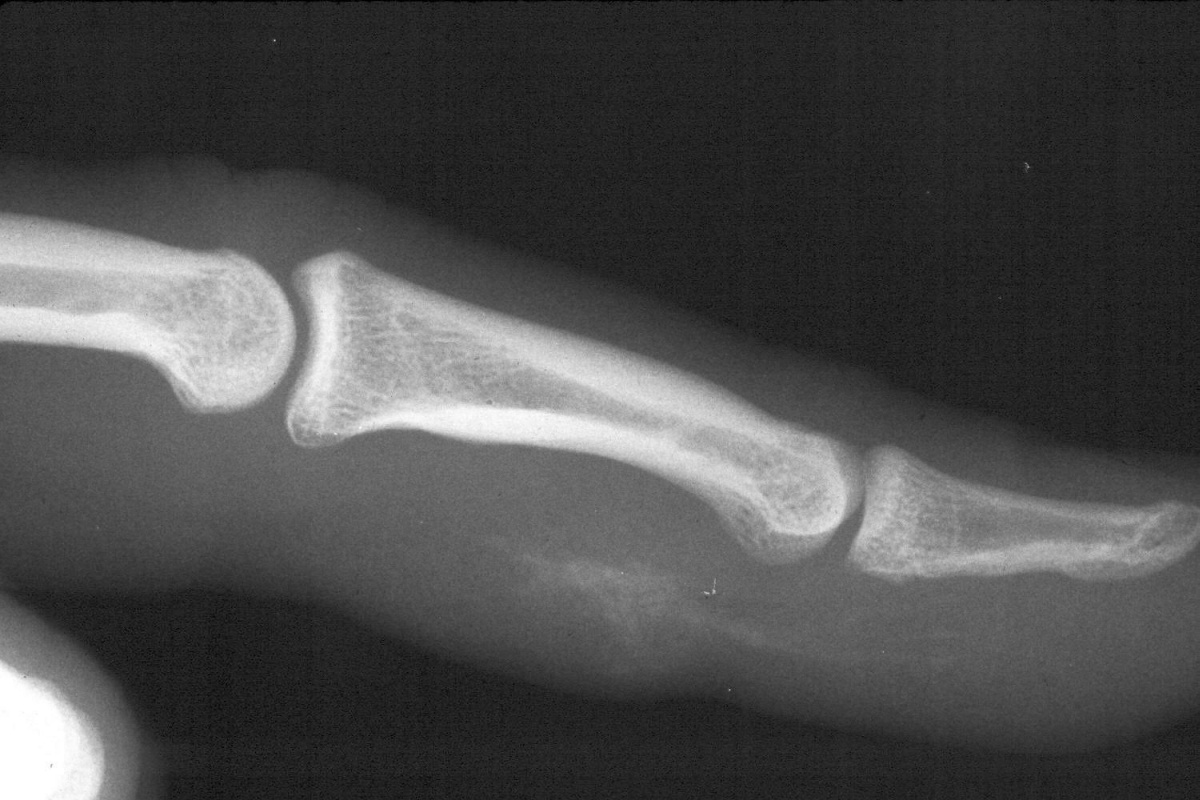

Case 1. Relatively low pressure white latex paint injection injury, Two hours earlier. Finger swelling, pain, stiffness, and a small entry wound.

Radiographs show titanium paint pigment.